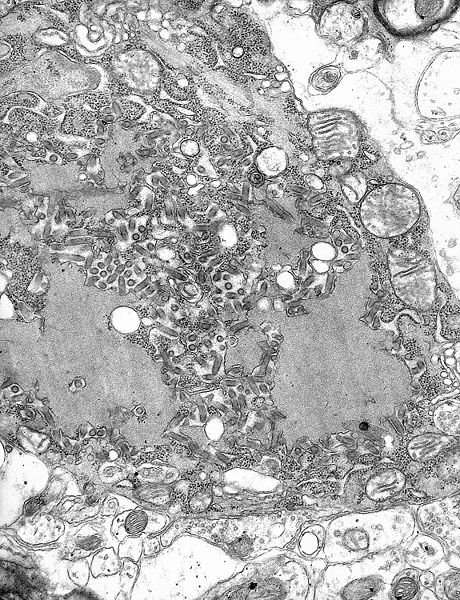

Kuduz hastalığının etkeni Rabies virüsüdür. Rabies virüs uygun şartlarda (0-4°C’ta) yıllarca stabil kalır. Güneş ışığı, ultraviole, X-ray ve deterjanlar ile kolayca etkisiz kalabilir. Bu bilgiler virüsün, uygun ortam bulduğu zaman vücut dışında da canlı kalabileceğini ve herhangi bir ısırık hikayesi olmadan insanları ya da hayvanları enfekte edebileceğini göstermektedir.